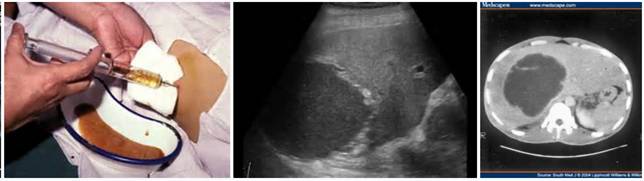

Chẩn đoán bệnh

-Trước đây, khi một chẩn đoán nghi ngờ áp xe gan do amip thì thủ thuật chọc dò gan vừa thăm dò, vừa chẩn đoán rất phổ biến và như một bước thường quy. Chọc dò là một xét nghiệm xâm lấn, gây đau và nguy hiểm vì amíp có thể theo kim chọc dò lây sang các mô khác của cơ thể;

-Nếu đúng là áp xe gan do amíp sẽ hút ra mủ màu sôcôla, thường rất khó tìm sự hiện diện amíp trong mủ vì dạng hoạt động ký sinh ở vách áp xe chứ không ở trong mủ;

-Siêu âm gan mật cho thấy hình ảnh đặc trưng của ổ áp xe có bờ rõ nhưng áp xe nhỏ quá đôi khi bỏ sót chẩn đoán. Khối áp xe thường ở các vị trí thuộc hạ phân thùy của gan phải, hiếm khi nhìn thấy ở thùy vuông hay hạ phân thùy 1, có lẽ do cấu trúc giải phẩu và tính ưu thế;

-Siêu âm bụng tổng quát khảo sát thấy mức dịch nhạy hơn trên phim chụp x - quang;